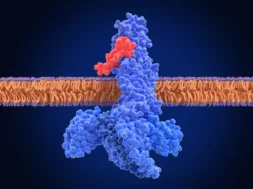

Το εγκεφαλικό επεισόδιο συμβαίνει όταν διαταράσσεται η παροχή αίματος στον εγκέφαλο. Τα περισσότερα περιστατικά οφείλονται στην απόφραξη μιας από τις αρτηρίες που στέλνουν αίμα στον εγκέφαλο ή σε κάποιο μικρό κλαδίσκο. Αυτός ο τύπος αναφέρεται ως «ισχαιμικό» επεισόδιο (από την λέξη «ισχαιμία» η οποία σημαίνει ανεπαρκή παροχή αίματος).

Εκτός όμως από το «ισχαιμικό»υπάρχει και το «αιμορραγικό» επεισόδιο το οποίο συμβαίνει ως αποτέλεσμα της ρήξης ενός αγγείου είτε μέσα είτε γύρω από τον εγκέφαλο.